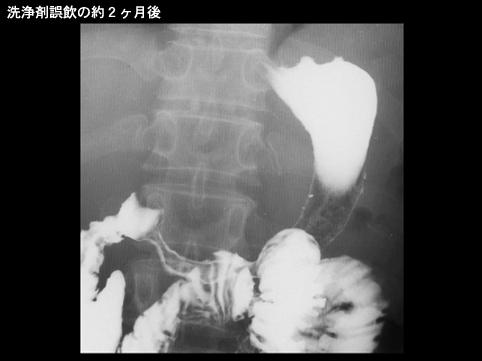

症例提示(所在地,施設名等): 東京都・ 社会保険中央総合病院 (Dr.浜田)

疾患(病理主体)の分類炎症性・潰瘍性疾患/腐蝕性胃炎

部位(臓器別)胃(部位)/2つ以上

検査方法X-P

病変の最大径(ミリ)40以上